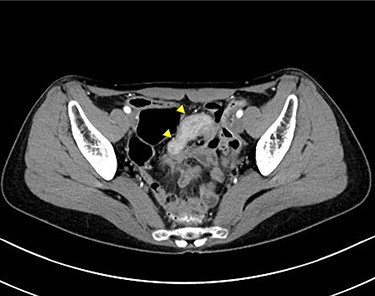

A 45-year-old woman was admitted with recurrent abdominal pain. She had no significant past medical history. Physical examination showed mild tenderness in the lower abdomen. Laboratory findings were within normal limits, except for serum carbohydrate antigen 19-9 (58 U/mL). Computed tomography (CT) scan showed a continuous lesion to the ileum with contrast enhancement (Fig. 1). Retrograde double-ballon enteroscopy showed an ulcerated lesion at 160 centimeters from the ileocecal valve, and biopsy showed well-differentiated adenocarcinoma (Fig. 2). An enteroscopy-assisted contrast study revealed intestinal stenosis involving a Meckel’s diverticulum (Fig. 3). Based on these findings, we diagnosed adenocarcinoma in a Meckel’s diverticulum preoperatively. Intestinal resection with lymph node dissection was performed. Operative findings showed that the tumor invaded the Meckel’s diverticulum 160 centimeters from the ileocecal valve. No findings of abdominal dissemination were observed (Fig. 4). Histological examination of the resected specimen revealed a well-differentiated adenocarcinoma, interrupted by ectopic gastric mucosa (one side shown, Fig. 5a.).

Computed tomographic scan showing a continuous lesion to the ileum with contrast enhancement (arrowheads).